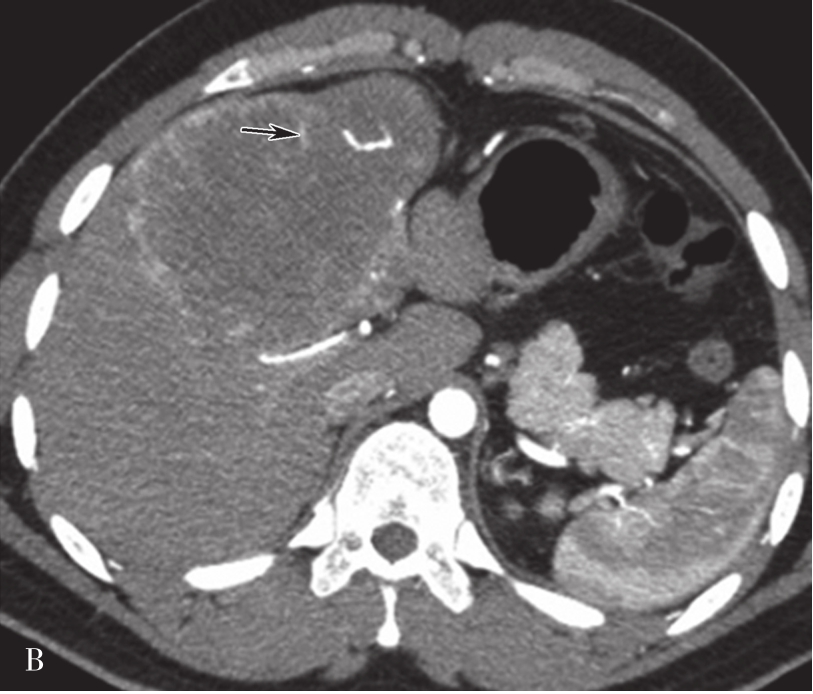

(2)CT表现:

巨块型和结节型平扫表现为单发或多发、圆形、类圆形或不规则形肿块,呈膨胀性生长,绝大多数肝癌边缘有假包膜,因而多数瘤灶边界清楚,这是肝细胞癌CT诊断重要征象;弥漫型者结节分布广泛,境界不清;小肝癌表现为肝实质内3cm以下类圆形肿块。肿块多数为低密度,少数表现为等密度,或在脂肪肝背景衬托下可呈高密度。巨块型肝癌可发生中央裂隙状坏死而出现更低密度区,合并出血或发生钙化,则肿块内表现高密度灶;有时肿块周围出现小的结节灶,称为子灶。多数肝癌主要由肝动脉供血,增强扫描动脉期,病灶通常出现明显的斑片状、结节状早期强化;在门静脉期,门静脉和肝实质明显强化,而肿瘤无或仅少量门静脉供血则强化程度迅速下降;平衡期,肝实质继续保持较高程度强化,肿瘤强化程度则继续下降而相对低密度表现,增强过程表现典型的“快进快出”的特征性改变(图5-21-38)。少数肝癌为门静脉供血为主者,其强化方式相对不典型。如在动态CT系列图像上分别测定CT值并绘制时间-密度曲线,可见肝癌强化的时间-密度曲线呈速升速降形曲线。肿瘤的假包膜一般呈延迟强化表现。有门静脉、肝静脉或下腔静脉癌栓者则增强门脉期或静脉期出现静脉内低密度充盈缺损,部分患者可见转移性腹膜后和肝门区的淋巴结肿大,以及远处转移。

图5-21-38 HCC患者的CT平扫及增强图像

A.CT平扫图像,肝右前叶内可见巨块状稍低密度影,大小约10.5cm×8.3cm,CT值为36~46HU,其内密度不均,界限欠清,病灶内可见更低密度影;B.增强扫描动脉期,病灶不均匀强化,CT值约69HU,并见多量小刷状不成熟肿瘤血管影(箭头);C.增强扫描门脉期图像,病灶密度略低于肝脏实质,CT值约68HU,病灶假包膜厚薄不均(箭头);D.3min延迟期图像,随着时间的延长,病灶密度低于肝脏实质,CT值64HU,中央低密度区未见明显强化;E.动脉期最大密度投影法重建图像示肝动脉分支明显增多供应病灶